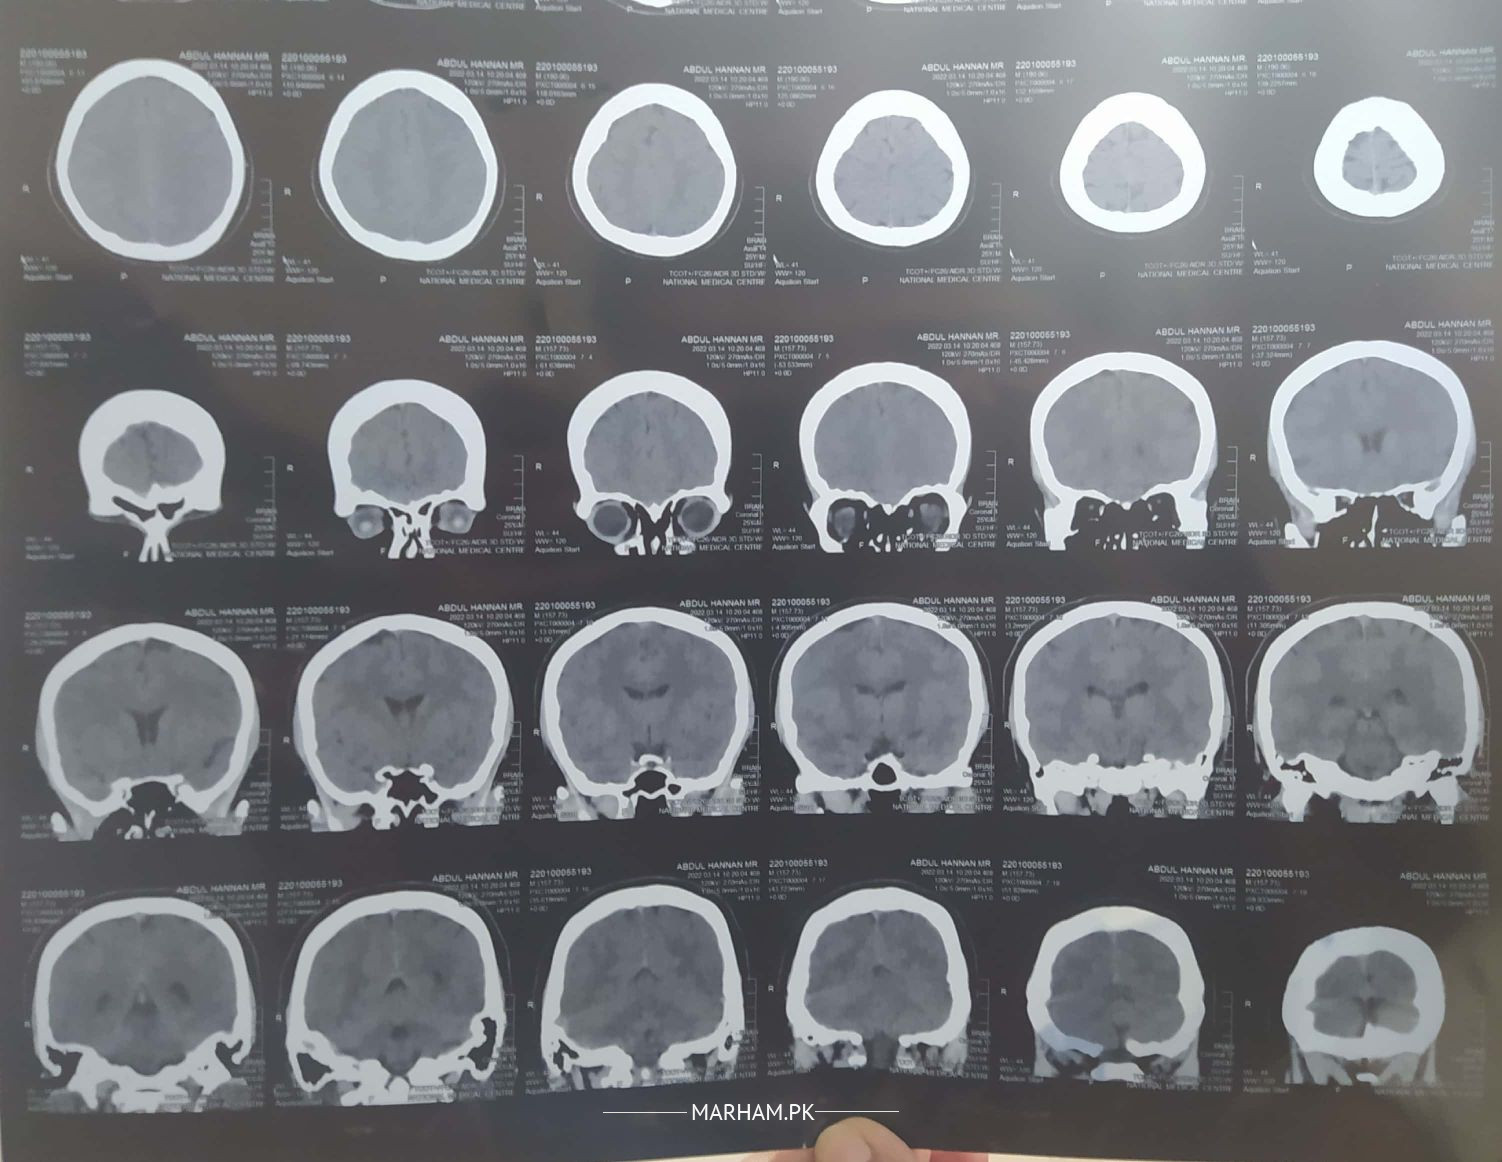

Went to doctor due to memory loss issues and constant headaches. He asked to do CT scan of brain. please review the ct scan, is there anything to worry about or it's normal?

ct looks normal. proper histry and examination needed. get proper chekup from nearby neurologist

normal CT....

ct seems ok

you need to be seen by neurologist or neurosurgeon physically

You need to consult with detailed history. Online consultation at Marham can be arranged but if you need fundoscopy you will need to consult a neurologist face to face

CT scan pe koi pareshani wali baat nahi. aap muaaina karwayain!